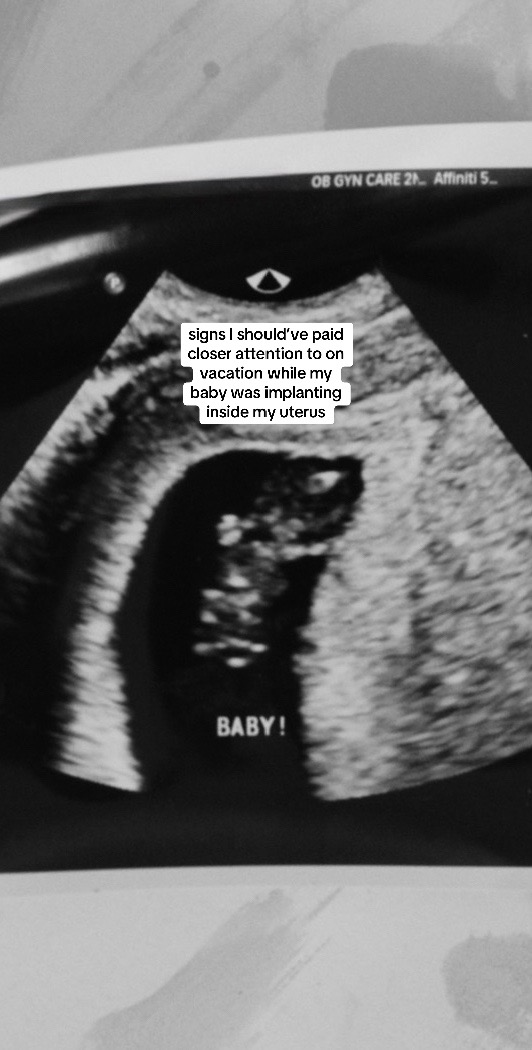

Our “inside joke” on our friend group’s Mexico trip earlier this summer was “babysitting these plastic babies” and bringing them everywhere with us... turns out I had my own REAL LIFE baby 😅